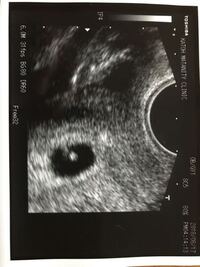

5 週 0 日 559337-5週0日 胎嚢 5mm

妊娠5週6日目のエコー写真と胎嚢の大きさ&費用 妊娠5週6日目のエコー写真と胎嚢の大きさ↓↓ 胎嚢(GS)は、143mmで 前回受診時(妊娠4週5日目)のときよりも大きくなっていました!!今日の時点では私は、5 weeks exactly (多分5週0日ということかな)で、胎嚢のサイズも5 weeks exactlyで、everything is normal と言われた。 前回は(またしても比べる私)、5週2日で78mmだったので、今回のが2日分大きい感じかな。5 34 6 35 妊 娠 5 週 0 高温相が3週間続いたら妊娠を考えましょう。 生理予定日から1週間後に妊娠検査薬を使えます。 36 1 37 2 38 3 39 4 40 5 41 6 42 妊 娠 6 週 0 5週目から心拍が確認されるようになります。 胎嚢の中に胎芽が観察されるようになり

5週0日。 基礎体温は3722℃。 今日は待ちに待った胎嚢確認の日です。 待ってはいたのですが、いざ確認となると不安でドキドキ。 無事、嚢が見えますように。 10時30分に予約をしていたので、お仕事は10時からお休みを頂き 旦那さまと一緒に病院へ。早くて土曜日になりますが、どうしますか? あれから出血は増えておら 5週0日 コロナ感染者の自宅療養記(軽症) 新型コロナウイルスに関する情報について